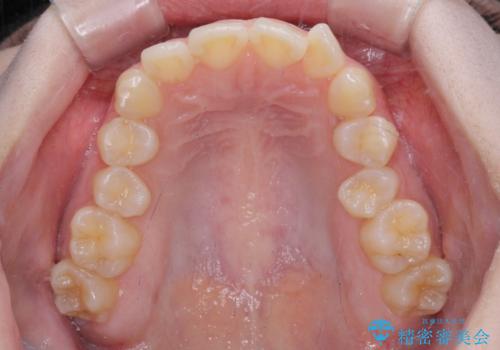

左上の前歯が出ているのが気になる 審美装置による非抜歯ワイヤー矯正

- 左上の前歯が出ていることを主訴として来院された患者様です。

当初はインビザラインを希望されていましたが、職業柄お茶する機会が多く装着時間を確保することが難しいとのことで、相談の上ワイヤー矯正の中では目立ちにくい審美装置で矯正を進めていくこととしました。